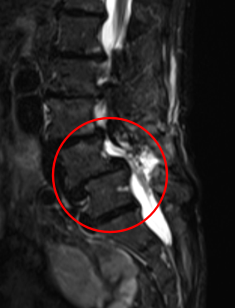

治療後

PEL実施から2週間経過したときには、お尻の痛み、痺れが軽減したとのことです。また治療から4ヶ月後には手術前の痛みと比べて、10から3へ、しびれは10から1になりました(※)。術後のMRIでも狭窄症の圧迫はきれいにとれていました。